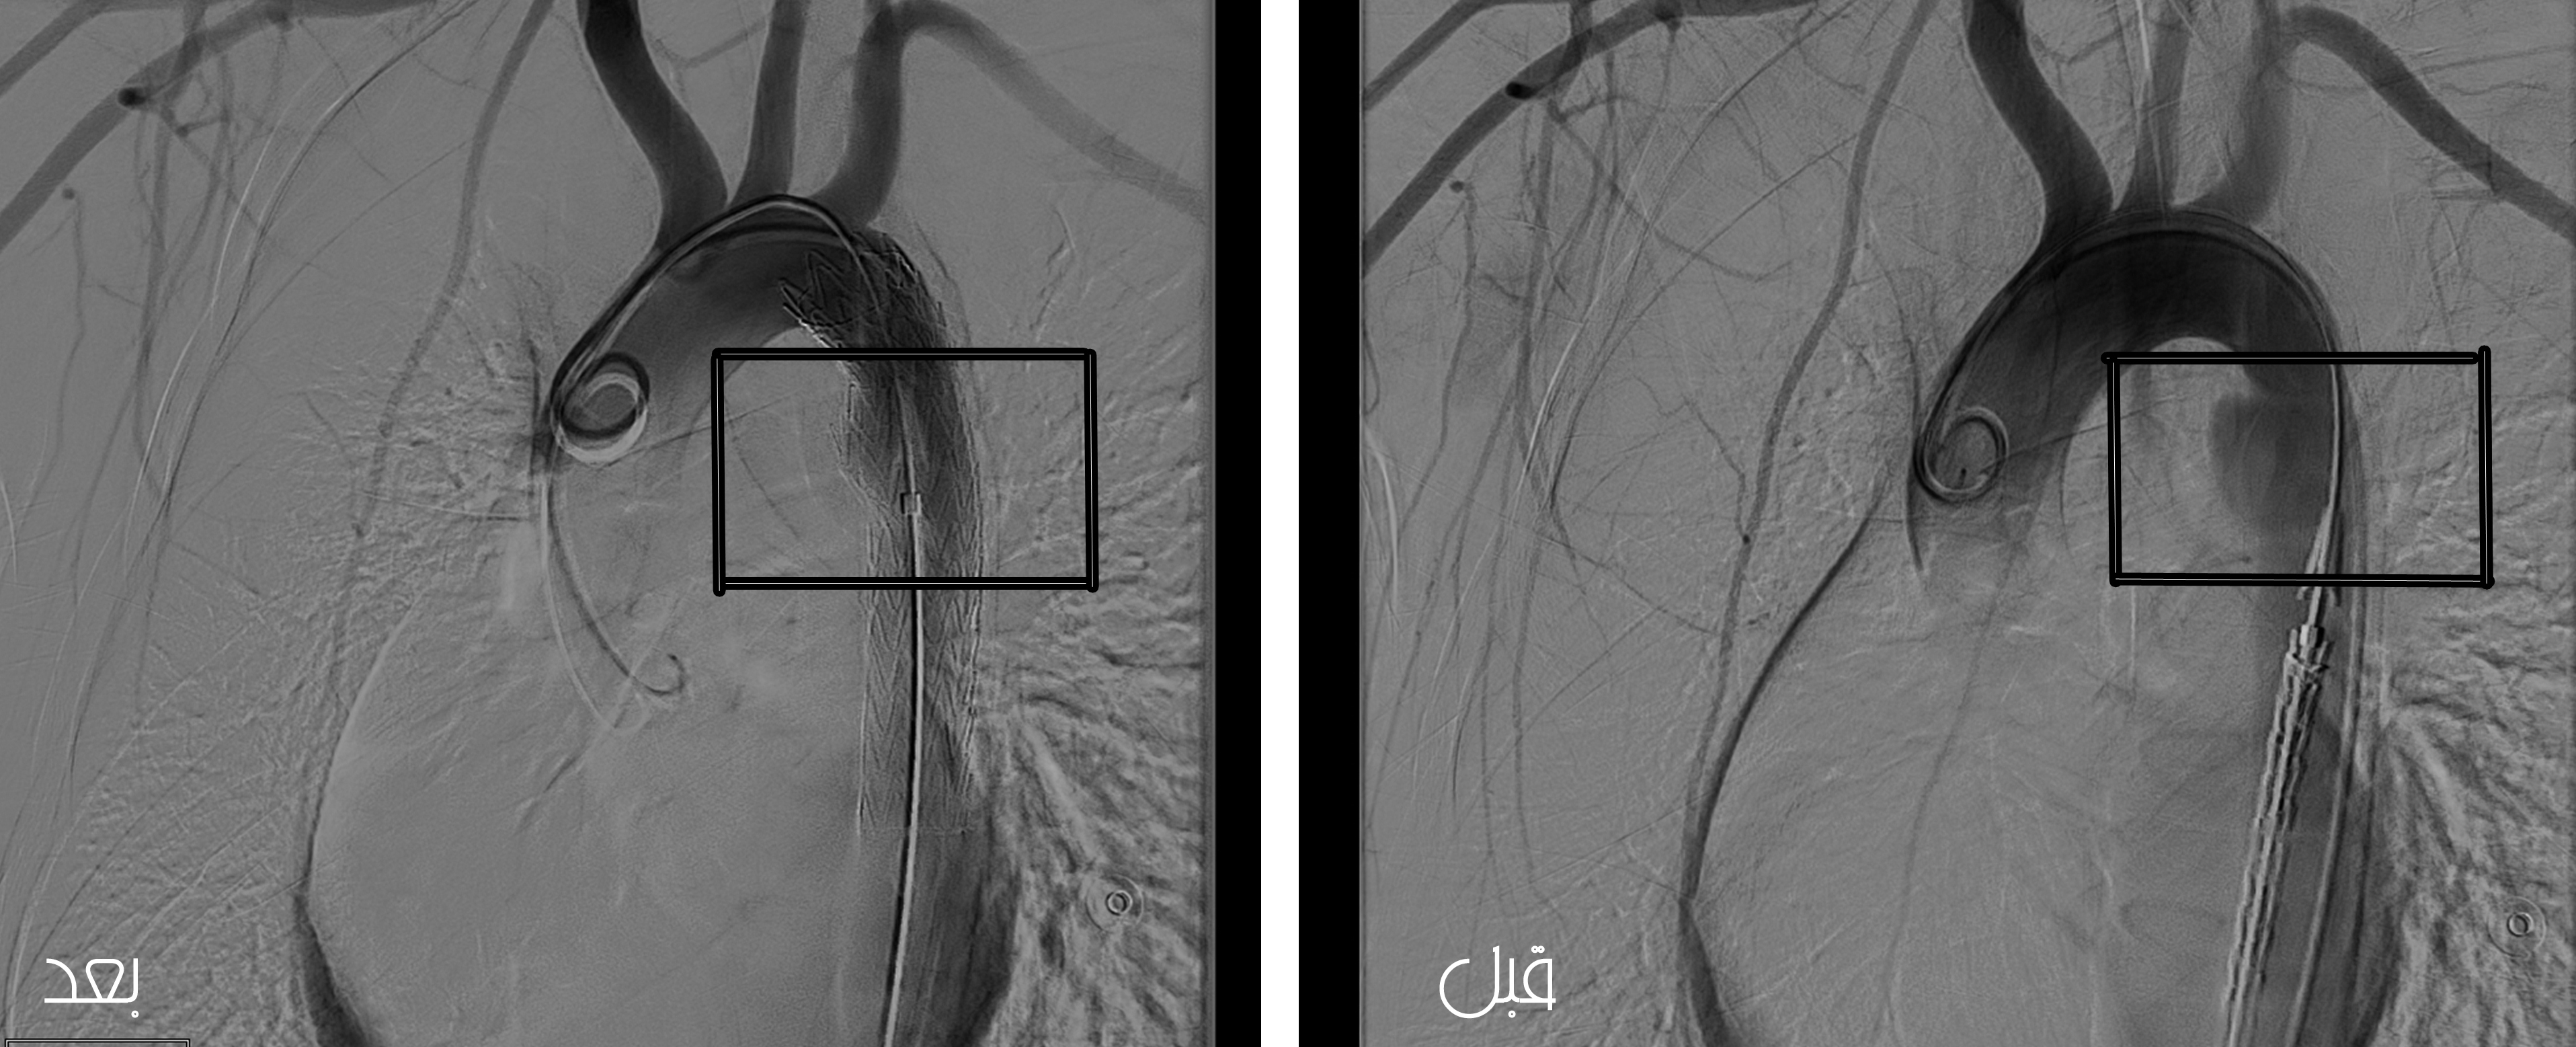

كشف المشرف العام على مستشفى الملك فهد المركزي بجازان الدكتور حسن الشعبي عن استقبال قسم الطوارئ حالة مريض شاب سعودي في العقد الثالث من العمر بعد تعرُّضه لحادث سير شديد؛ أدى إلى كسور في الجمجمة وإصابة من الدرجة الأولى للكبد مع تمزق في الشريان الأورطي الصدري، وحيث إن هذا التمزق قابل للانفجار في أي لحظة؛ مما قد يؤدي إلى وفاة المريض لا سمح الله.

مضيفاً أنه تم تحضير المريض وإجراء الإسعافات الأولية له، ثم نُقل إلى وحدة الأشعة التداخلية المجهزة بأجهزة تصوير شعاعي حديثة “غرفة عمليات هجينة” وبعد التصوير اللازم وجدت الإصابة على مستوى الشريان الأورطي الصدري النازل، وعلى الفور قام الأطباء المعالجون بإدخال دعامة اصطناعية عن طريق فتحة صغيرة في الفخذ لا يتعدى طولها 1سم وتم زرعها في الشريان الأورطي، وبذلك تم عزل الإصابة وترميمها لتستقر حالة المريض بعد العمل الجراحي وأوصى الأطباء بإخراجه من العناية المركزة ليستكمل ما تبقى من العلاج اللازم مع بقية التخصصات الأخرى حسب الإصابة.

وأكد الشعبي أن هذا العمل الجراحي من العمليات المعقدة التي تُجرى لأول مرة بمنطقة جازان، والتي تمت بمشاركة وحدتي الأشعة التداخلية وجراحة الأوعية الدموية وفريق التخدير في المستشفى، وهم من أصحاب الكفاءات المميزة متمنين الشفاء العاجل للمريض.